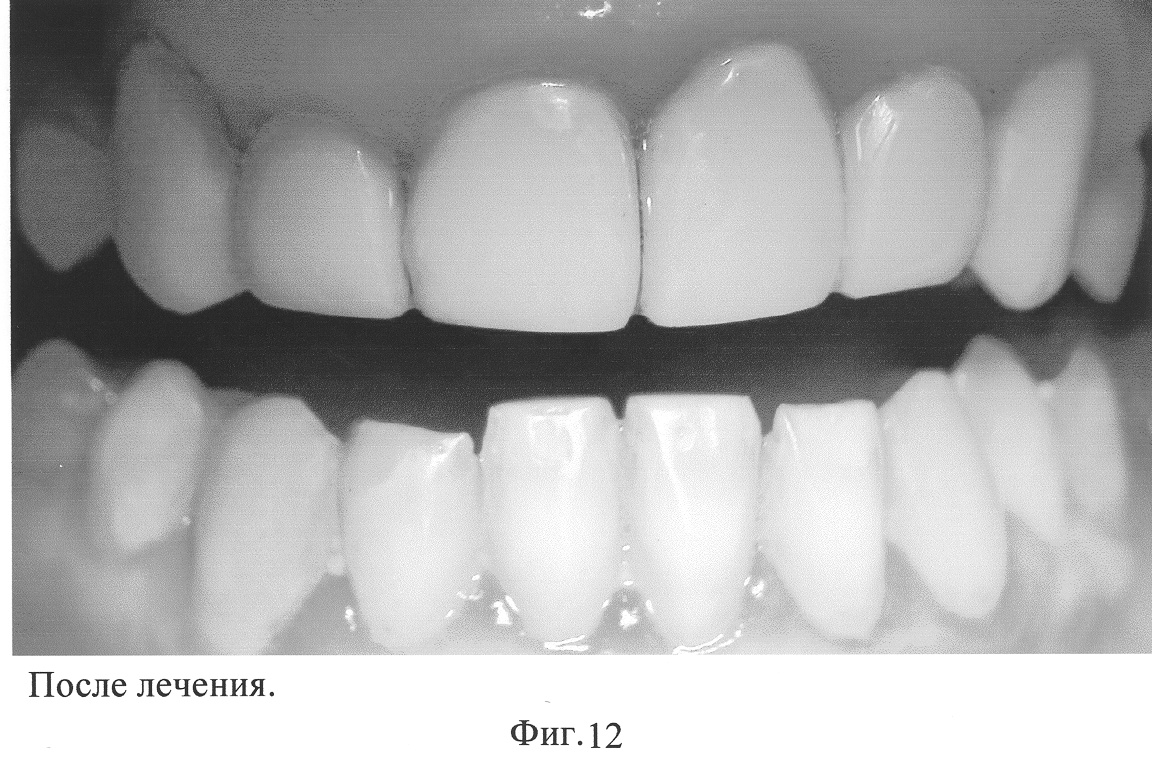

Лечение: Определяли цвет будущей реставрации по шкале VITA. Произвели ретракцию десны ретракционной нитью. После ретракции десны на основании корня сформировали полость. Армирующий штифт изготавливали из прямоугольной пластины, выполненной из металлической сетки. Из пластины формировали армирующую и фиксирующую части штифта. Противоположные стороны по длине пластины сближали друг относительно друга для придания пластине изогнутой формы. Ширина армирующей части штифта соответствовала ширине дефекта коронковой части отсутствующего зуба. Со стороны, противоположной армирующей части штифта, формировали ее фиксирующую часть. Для этого пластину изгибали дополнительно для придания ей формы, повторяющей форму полости, сформированной на основании корня.

Металлическим нитям, выкроенным из сетки, придавали “U”-образную форму. Свободные концы нитей пропускали через отверстия фиксирующей части штифта, скручивали их между собой, жестко соединяя с фиксирующей частью штифта. После примерки и коррекции сборного армирующего сеточного штифта производили кислотное травление основания корня, при этом корневой канал закрывали ватой. Кислоту смывали струей воды при работающем слюноотсосе, полость высушивали воздухом, наносили адгезив, слегка продували воздухом для равномерного распределения. Полимеризовали стандартным методом согласно инструкции. Далее удаляли вату из корневого канала и штифт фиксировали с помощью стеклоиномерного цемента, размещая в корневом канале элемент крепления, а в сформированной полости основания корня – фиксирующую часть штифта.

После фиксации сборного армирующего штифта приступали к окончательной реставрации отсутствующей коронковой части зуба в соответствии с его анатомической формой с применением композитных материалов.

Эстетический эффект достигали после предварительной обработки и шлифовки стандартными полировочными дисками различной толщины и зернистости абразива, алмазными борами, а апроксимальные поверхности обрабатывали штрипсами. Окклюзионное редактирование проводили под контролем окклюзионной бумаги финишными борами, дисками. Удаляли ретракционную нить. Осложнений после проведения вышеуказанным способом выявлено не было.